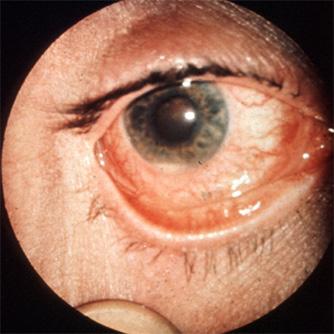

Síntomas oculares, como conjuntivitis y, con menor frecuencia, uveítis anterior, epiescleritis y queratitis. (Ver Figura 16)